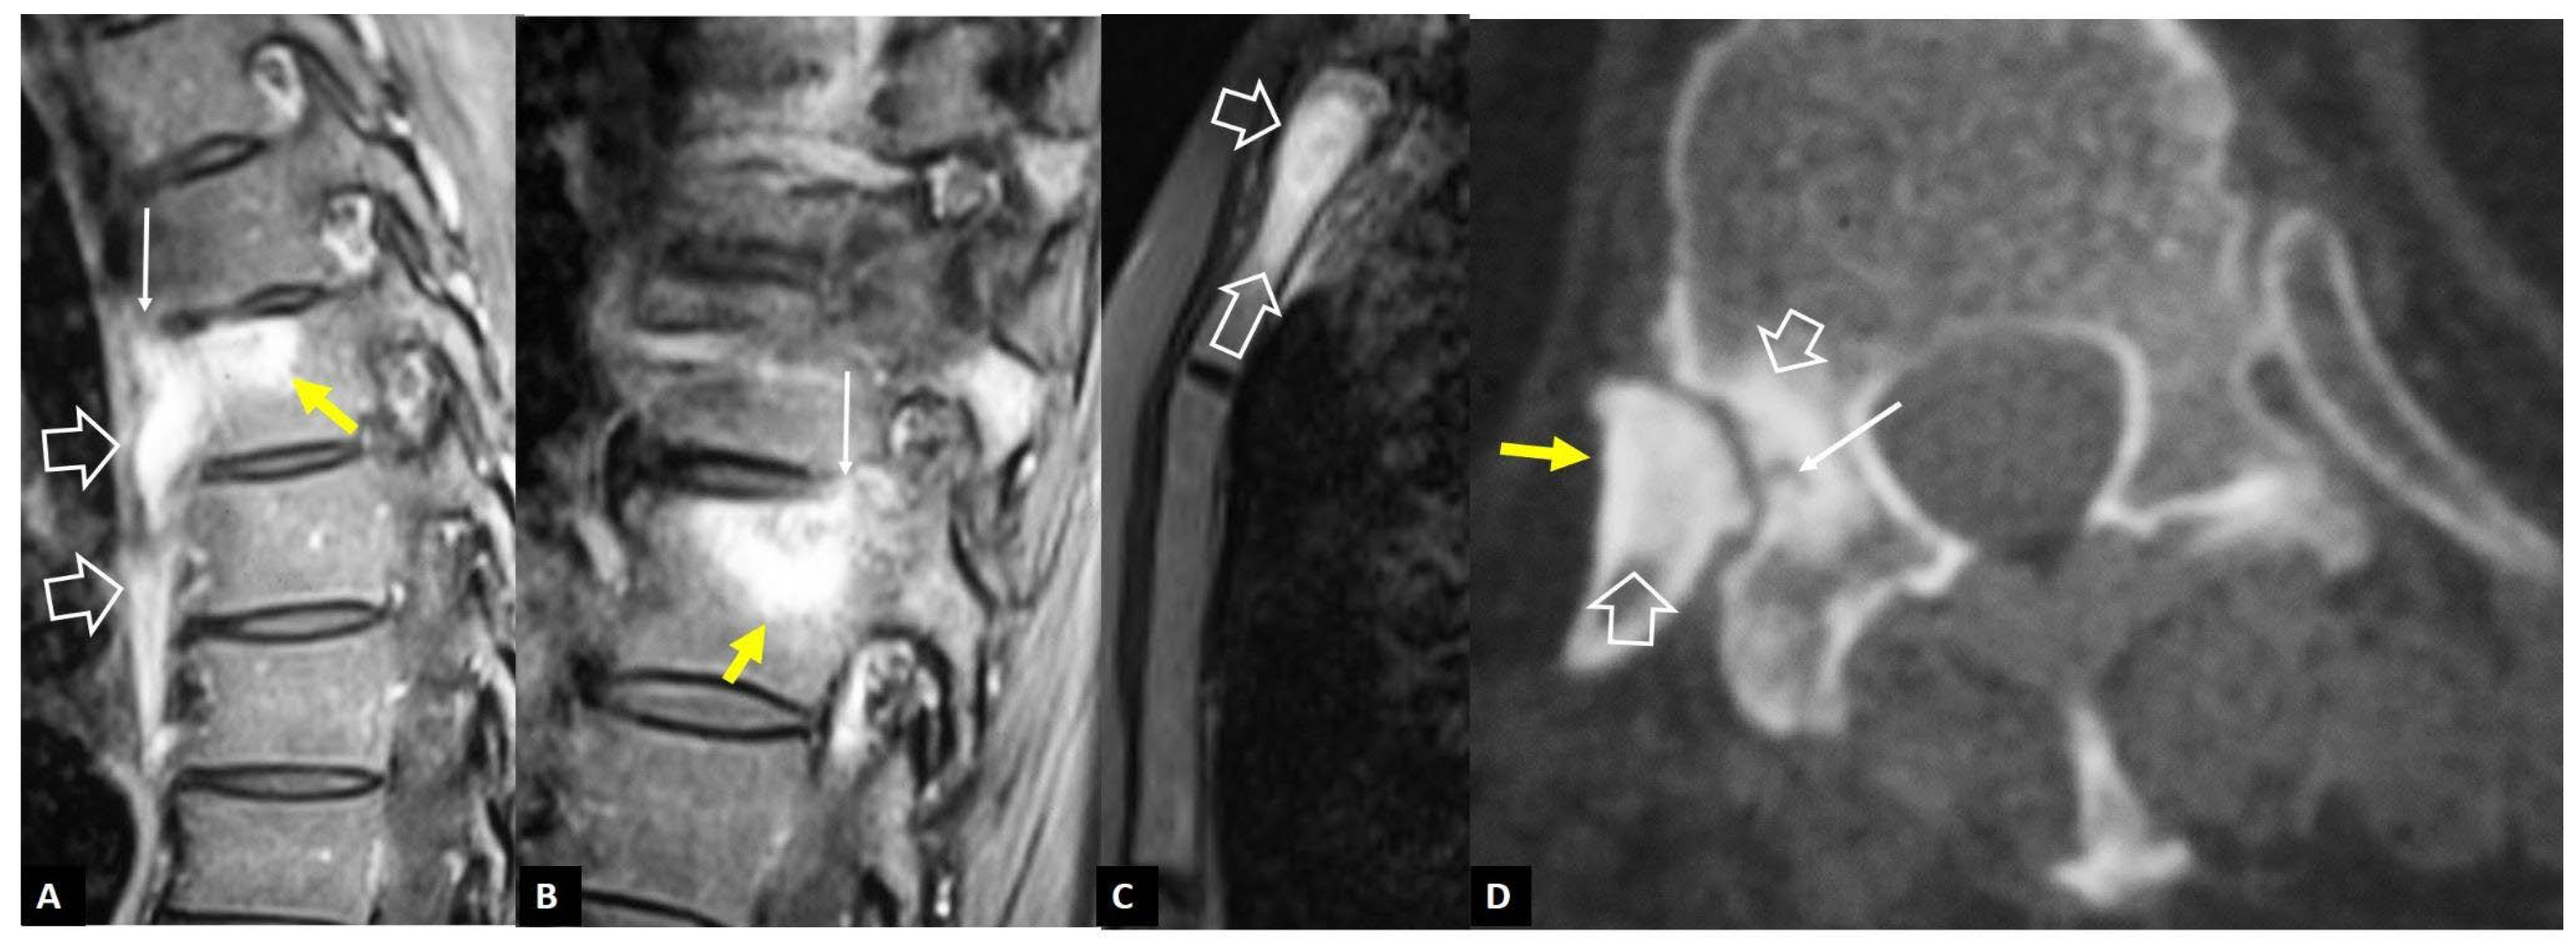

1. a.ii. Aseptic Spondylodiscitis

1. a.iii. SAPHO Syndrome

1. a.iv. Destructive Spondyloarthropathy

1. a.v. Crystal Deposition